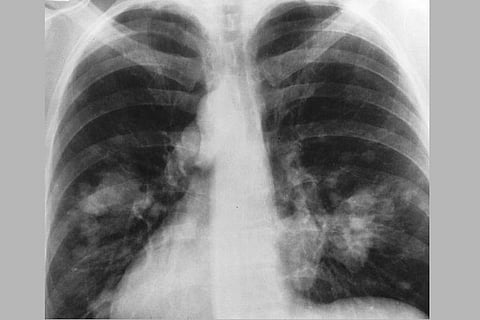

Tuberculosis is an infectious disease which is caused by the bacterium Mycobacterium tuberculosis. It is transmitted via air droplets from an infected individual to others. The initial symptoms of tuberculosis are fever, cough, cold, loss of weight and appetite, chest pain, as well as chills.